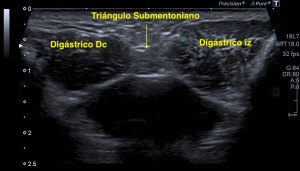

Siempre que tengas la oportunidad debes de usar el lado contralateral para salir de dudas…mira que imagen más preciosa vas a ver ahora, de ambos canales del cubital. Comparativas:

Compara ambas localizaciones, ambos nervios, como cambia el aspecto del izquierdo en comparación con el derecho y como en este, en el derecho, no existe en músculo ancóneo apitroclear. Derecho normal, izquierdo patológico.